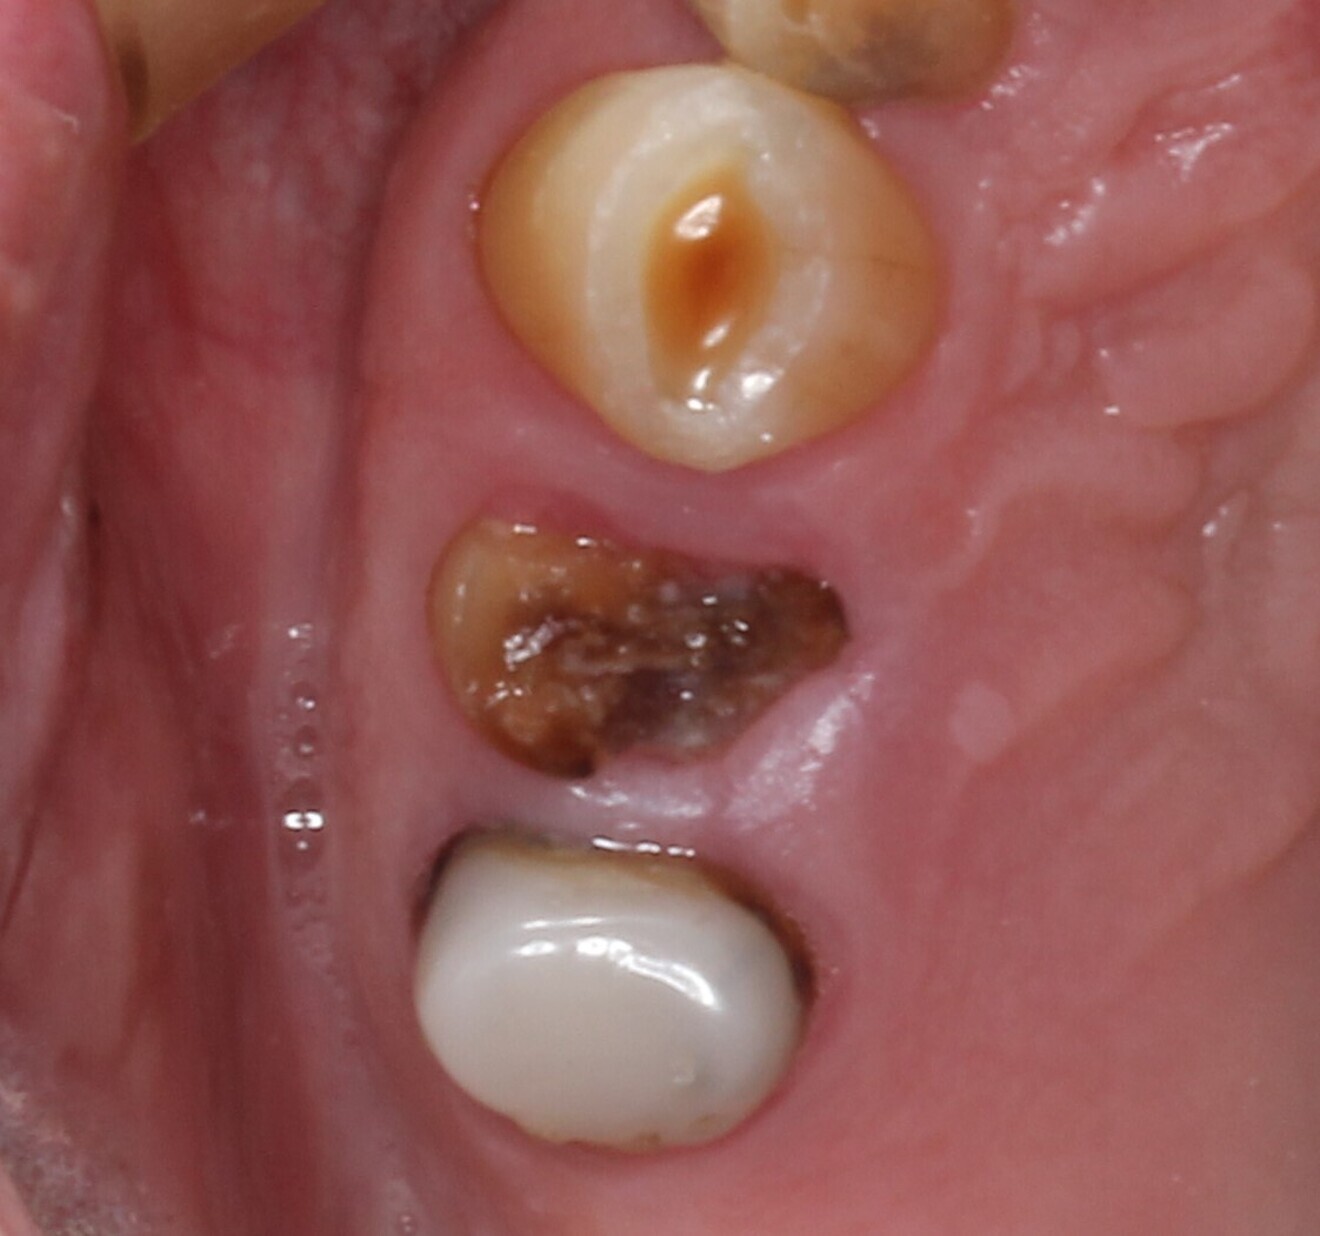

A male patient presented in our dental office with a severely broken maxillary right first premolar (tooth #14) that had been designated for extraction a number of years before. The tooth immediately distal (tooth #15) was also in need of substantial dental treatment (Figs. 1 & 2). The patient had hypertension that was controlled with anti-hypertensive medication, but was otherwise medically fit. He intended to have the colour of his anterior teeth improved, but wished to address the issues on his maxillary right side first.

Tooth #14 was deemed unrestorable, and so it was decided to extract the tooth (Figs. 3 & 4), wait for bony healing and replace it with an implant with a provisional restoration. During the healing process, endodontic therapy would be performed on tooth #15. After bony integration, implant #14 would be restored with a screw-retained direct-to-implant zirconia crown, and tooth #15 would also be restored with a complete zirconia crown. A deliberately lighter shade would be chosen, factoring in the patient’s long-term desire to improve the colour of his teeth.

Fig. 4: Post-extraction site.